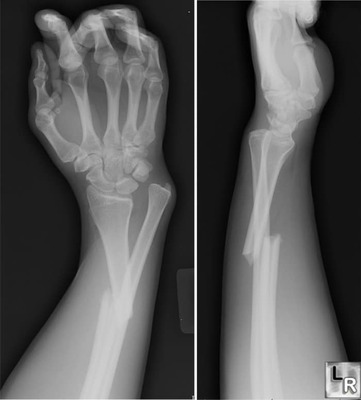

¿Cuantos Huesos Tiene La Mano Y La Muñeca Humana?

27

26

30

18

¿Es Una Fractura?

¿Que Tipo De Patología Consideras Que Es?

Esquince

Fractura

Luxación

Hernia Discal